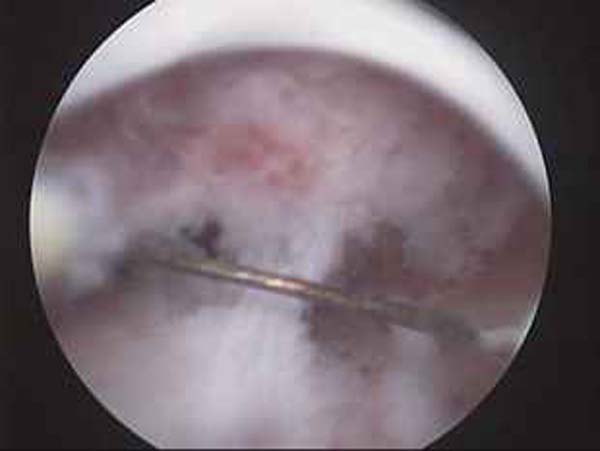

- Hystéroscopie - Hystéroscopie pour l'infertilité

- Résection hystéroscopique d'un septum utérin pour fausses couches à répétition

- Photos de l’hystéroscopie